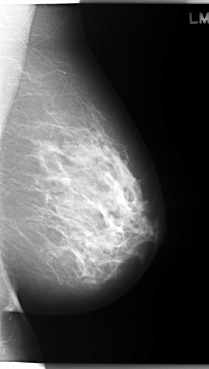

C_0032_1.LEFT_CC

LEFT_CC LINES 5968 PIXELS_PER_LINE 3520 BITS_PER_PIXEL 12 RESOLUTION 50 NON_OVERLAY